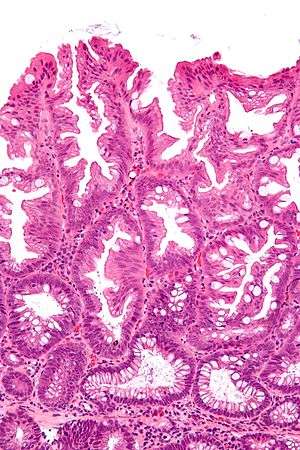

| Micrograph of a sessile serrated adenoma. H&E stain. | |

SSAs are diagnosed by their microscopic appearance; histomorphologically, they are characterized by (1) basal dilation of the crypts, (2) basal crypt serration, (3) crypts that run horizontal to the basement membrane (horizontal crypts), and (4) crypt branching. The most common of these features is basal dilation of the crypts.

Unlike traditional colonic adenomas (e.g. tubular adenoma, villous adenoma), they do not (typically) have nuclear changes (nuclear hyperchromatism, nuclear crowding, elliptical/cigar-shaped nuclei).